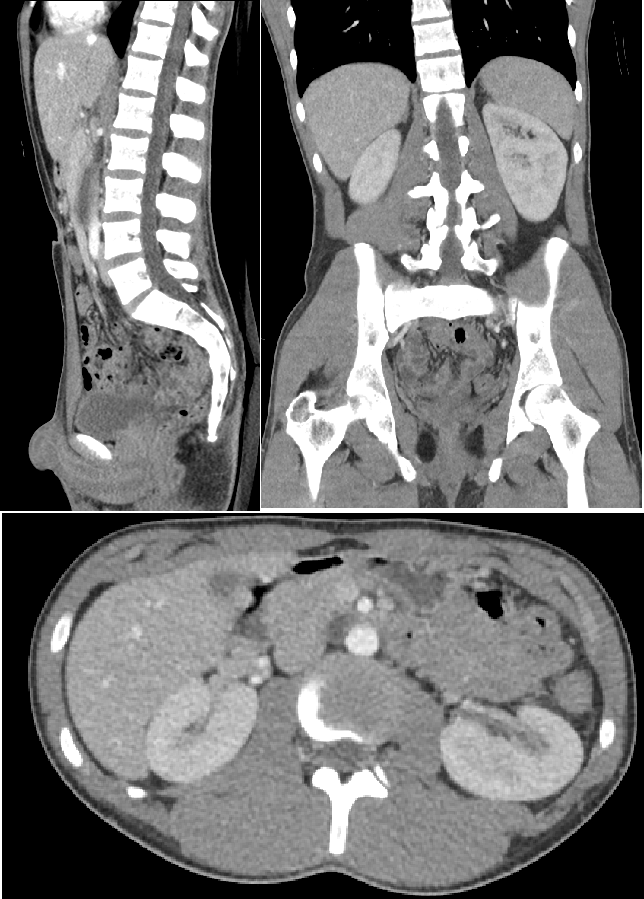

is this a CT or MRI

CT